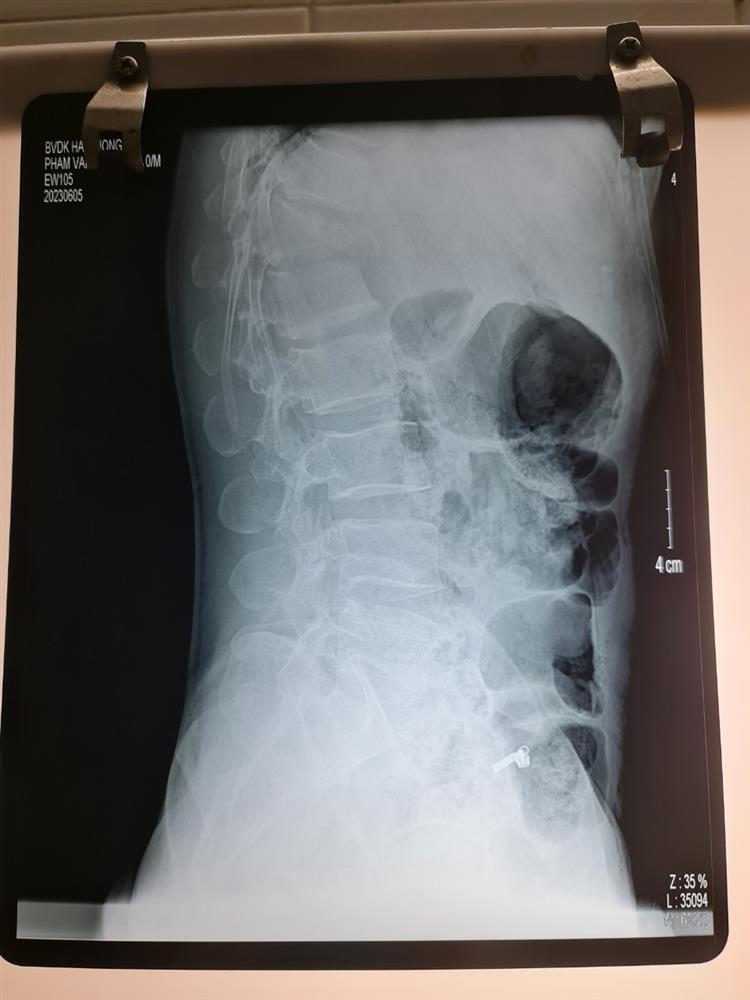

Anh Q vào viện do ngã cây vải đau nhiều cột sống thắt lưng, liệt hoàn toàn 2 chi dưới đã được các bác sĩ khoa cấp cứu BVĐK Tỉnh Hải Dương khám, cố định cột sống, chụp chiếu chẩn đoán CTCS gãy D12 L1 mất vững Frankel A , a đã được các bác sĩ hội chẩn và được các bác sĩ khoa ngoại 2 Phẫu thuật cấp cứu làm vững cột sống, giải ép tủy, khâu phục hồi màng tủy. Sau 10 ngày điều trị hiện tại sức khỏe của anh Q ổn định và được tập phục hồi chức năng, tuy đã phẫu thuật nhưng do tổn thương của anh Q phức tạp tổn thương tủy sống nên sự hồi phục vận động và cảm giác của a Q rất chậm và cần phải có một thời gian rất dài.